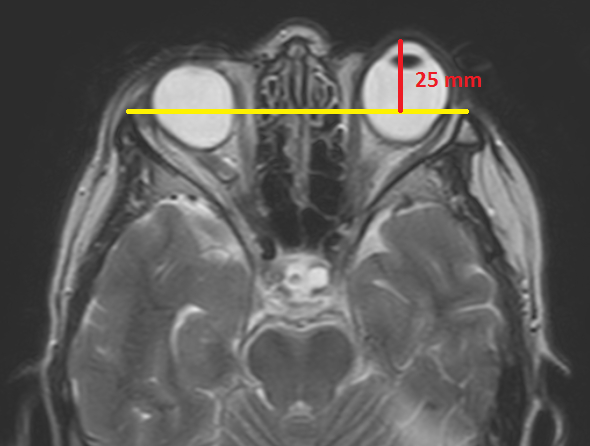

La propotsis puede cuantificarse empleando cortes axiales de TC o RM, donde se aprecie al globo ocular en sus diámetros máximos (incluso en forma prenatal).27,28,29,30

Para ello, se traza una línea recta entre los dos procesos cigomáticos (línea intercigomática). Luego se realiza otra línea (perpendicular a la intercigomática) hacia la esclera posterior: el valor promedio normal es 9,9 +/- 1,7mm (►Fig. 11).27,28,29,30

La distancia entre la línea intercigomática y el borde anterior del globo ocular debe ser menor a 21-23 mm (►Fig. 12).27,28,29,30